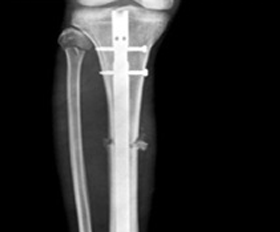

대퇴골 원위부 골절 >

금속판 1개 : 12~18개월

금속판 2개 : 18개월 이후 6월 간격

단계적 제거

골수정 : 24~36개월